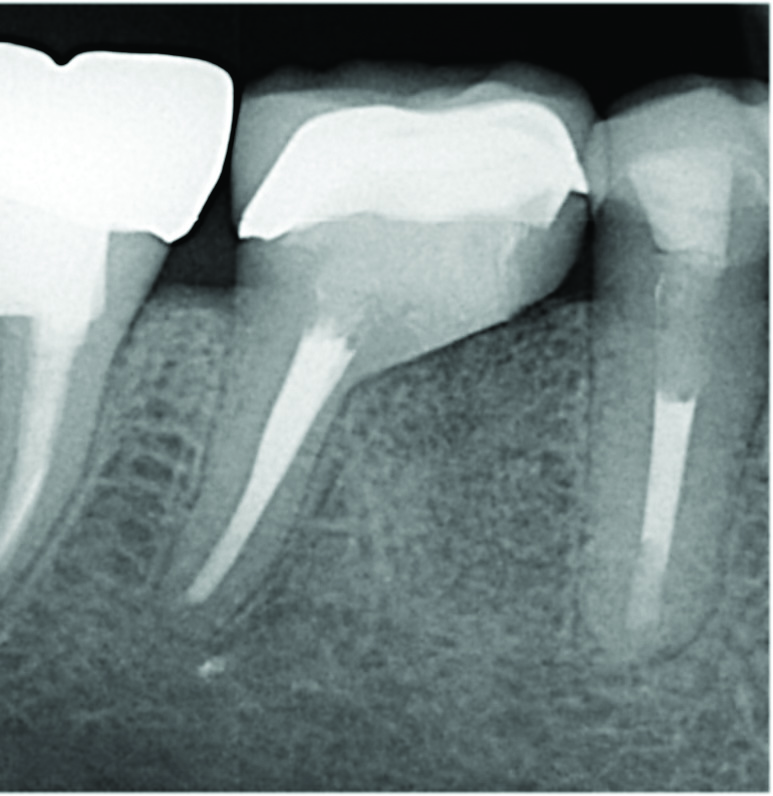

Fig 1 through Fig 4. Examples of multirooted teeth showing periradicular periodontitis and loss of periradicular bone support isolated to one root (indicated by red arrows). Fig 1: Tooth No. 3 distobuccal root with circumferential bone loss from the crestal bone height to the apex with stable mesiobuccal and palatal roots. Fig 2: Tooth No. 30 with a prior apical surgery showing bone loss surrounding a fractured mesial root. Fig 3: Tooth No. 19 with lateral and apical bone loss regions affecting a fractured mesial root. Fig 4: 3D CBCT imaging of tooth No. 3 depicting an apicomarginal bone loss defect affecting the mesiobuccal root with stable fused distobuccal and palatal roots.

Fig 4. Examples of multirooted teeth showing periradicular periodontitis and loss of periradicular bone support isolated to one root (indicated by red arrows). Fig 1: Tooth No. 3 distobuccal root with circumferential bone loss from the crestal bone height to the apex with stable mesiobuccal and palatal roots. Fig 2: Tooth No. 30 with a prior apical surgery showing bone loss surrounding a fractured mesial root. Fig 3: Tooth No. 19 with lateral and apical bone loss regions affecting a fractured mesial root. Fig 4: 3D CBCT imaging of tooth No. 3 depicting an apicomarginal bone loss defect affecting the mesiobuccal root with stable fused distobuccal and palatal roots.